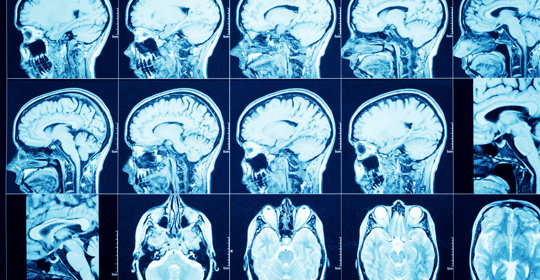

橋腦出血:中風復健方法與時間

橋腦出血:處理與預防措施

橋腦出血:治療措施與緊急性

橋腦出血:差異與治療